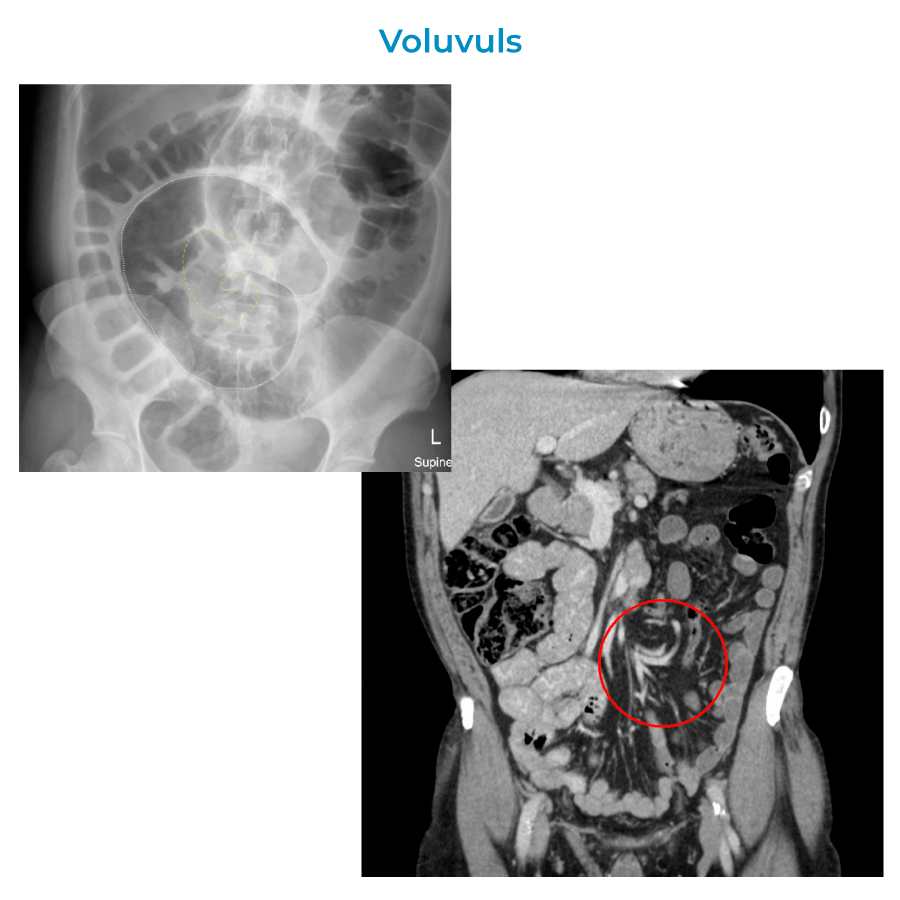

Other structural abnormalities include intussusception, volvulus, and congenital malrotations.

Volvulus